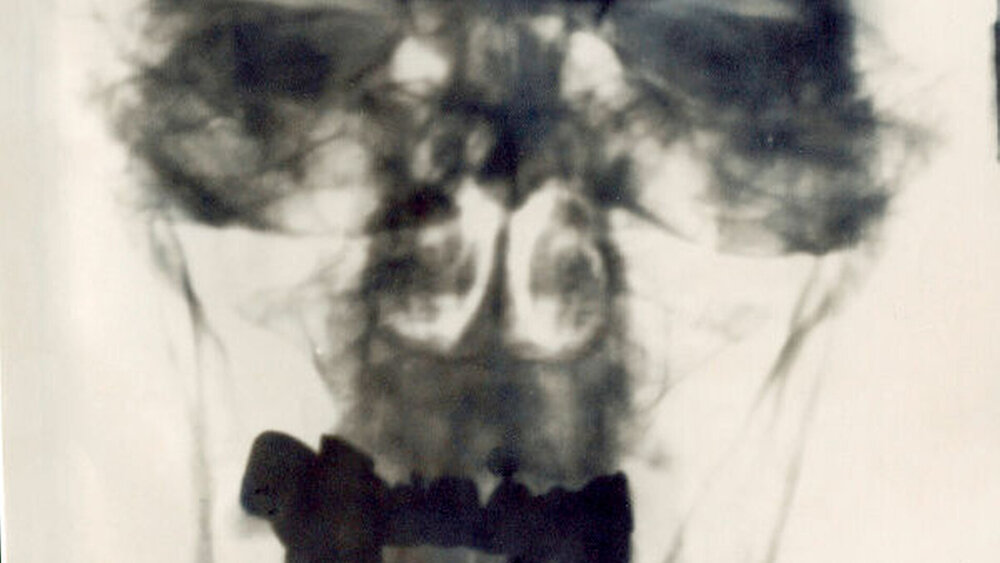

Der Erste, der den Fall Hitler aus kriminalistischer Sicht untersuchen durfte, war der Kölner Kriminal-Biologe Dr. Mark Benecke. Im November 2001 flog er nach Moskau, um ein Schädelfragment sowie Zahnreste und Prothesenteile zu untersuchen. Sein Urteil: An der Echtheit der Zähne gibt es keinen Zweifel. "Anhand von alten Röntgenaufnahmen konnte ich die Zähne eindeutig Hitler zuordnen", sagte er damals der Presse.

Auf den Röntgenbildern sei die ausgefallene Brücke Hitlers leicht zu erkennen. Spuren von Gift oder Glassplittern einer Gift-Ampulle fand Benecke damals an Hitlers Gebiss aber nicht. Aus Beneckes Sicht der Beleg, dass Hitler kein Gift genommen habe, um sich umzubringen.

Charlier, der schon zahlreiche Überreste prominenter Despoten analysiert hat und den Spitznamen "Indiana Jones der Friedhöfe" trägt, konnte die Zahnreste nun noch einmal mittels Abgleich mit den Röntgenbildern eindeutig Adolf Hitler zuordnen und bestätigt ein seit 1946 bekanntes Indiz für die Vergiftungstheorie. So fanden der Wissenschaftler und sein Team bläuliche Ablagerungen - die auch schon Krajewskij beschrieb, der zudem Glassplitter im Mund der Leiche erwähnte.